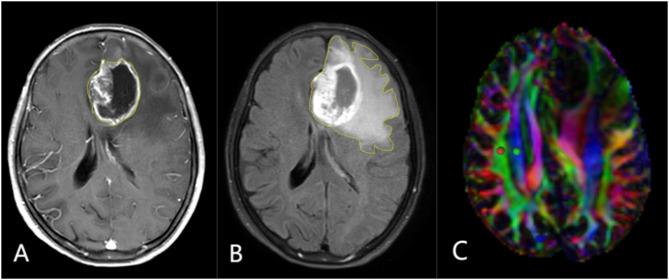

This study seeks to determine if patients with high-grade glioma (HGG) demonstrate glymphatic system (GS) impairments using Diffusion Tensor Imaging Along Perivascular Spaces (DTI-ALPS). Additionally, it aims to examine the factors affecting GS performance and their implications for HGG prognosis.

The study enrolled fifty HGG patients alongside fifty age- and sex-matched healthy individuals. Each participant underwent diffusion tensor imaging with a Philips 3.0T MRI scanner to assess and compute the ALPS index within perivascular spaces. Variables such as gender, grade, location, volume, peritumoral edema volume, mass-edema index (peritumoral edema volume/tumor volume) and ALPS index were recorded. The Student's t-test and rank sum test compared the ALPS indices between HGG patients and healthy controls to evaluate hemispheric differences. Linear and multivariate Cox regression analyses were utilized to discern factors influencing the ALPS index and to establish independent prognostic markers for HGG, respectively.

The ALPS indices in both hemispheres were significantly lower in HGG patients, with the ipsilateral hemisphere exhibiting further reduced levels than the contralateral (P < 0.001). In comparisons involving tumor and edema volumes, no significant variations were observed between the hemispheres within HGG patients harboring larger tumors (P = 0.079) or lesser edema volumes (P = 0.24). A decrease in postoperative ALPS indices compared to preoperative figures was noted (P < 0.001). Univariate linear regression indicated a negative relationship between the ipsilateral ALPS index and peritumoral edema volume (P = 0.0392). Kaplan-Meier analysis demonstrated shorter survival times in patients with lower ALPS indices. Moreover, multivariate Cox regression highlighted tumor grade (HR = 1.548, P = 0.023) and ipsilateral ALPS index (HR = 0.040, P = 0.003) as crucial prognostic indicators.

In patients with HGG, there is impaired GS function in both hemispheres of the brain. Additionally, the impaired GS function in the tumor-side hemisphere is associated with tumor-associated edema. Following surgery, further damage to GS function is observed in both hemispheres of the brain in HGG patients. Poor GS function in the tumor-side hemisphere is correlated with a worse prognosis in HGG patients.